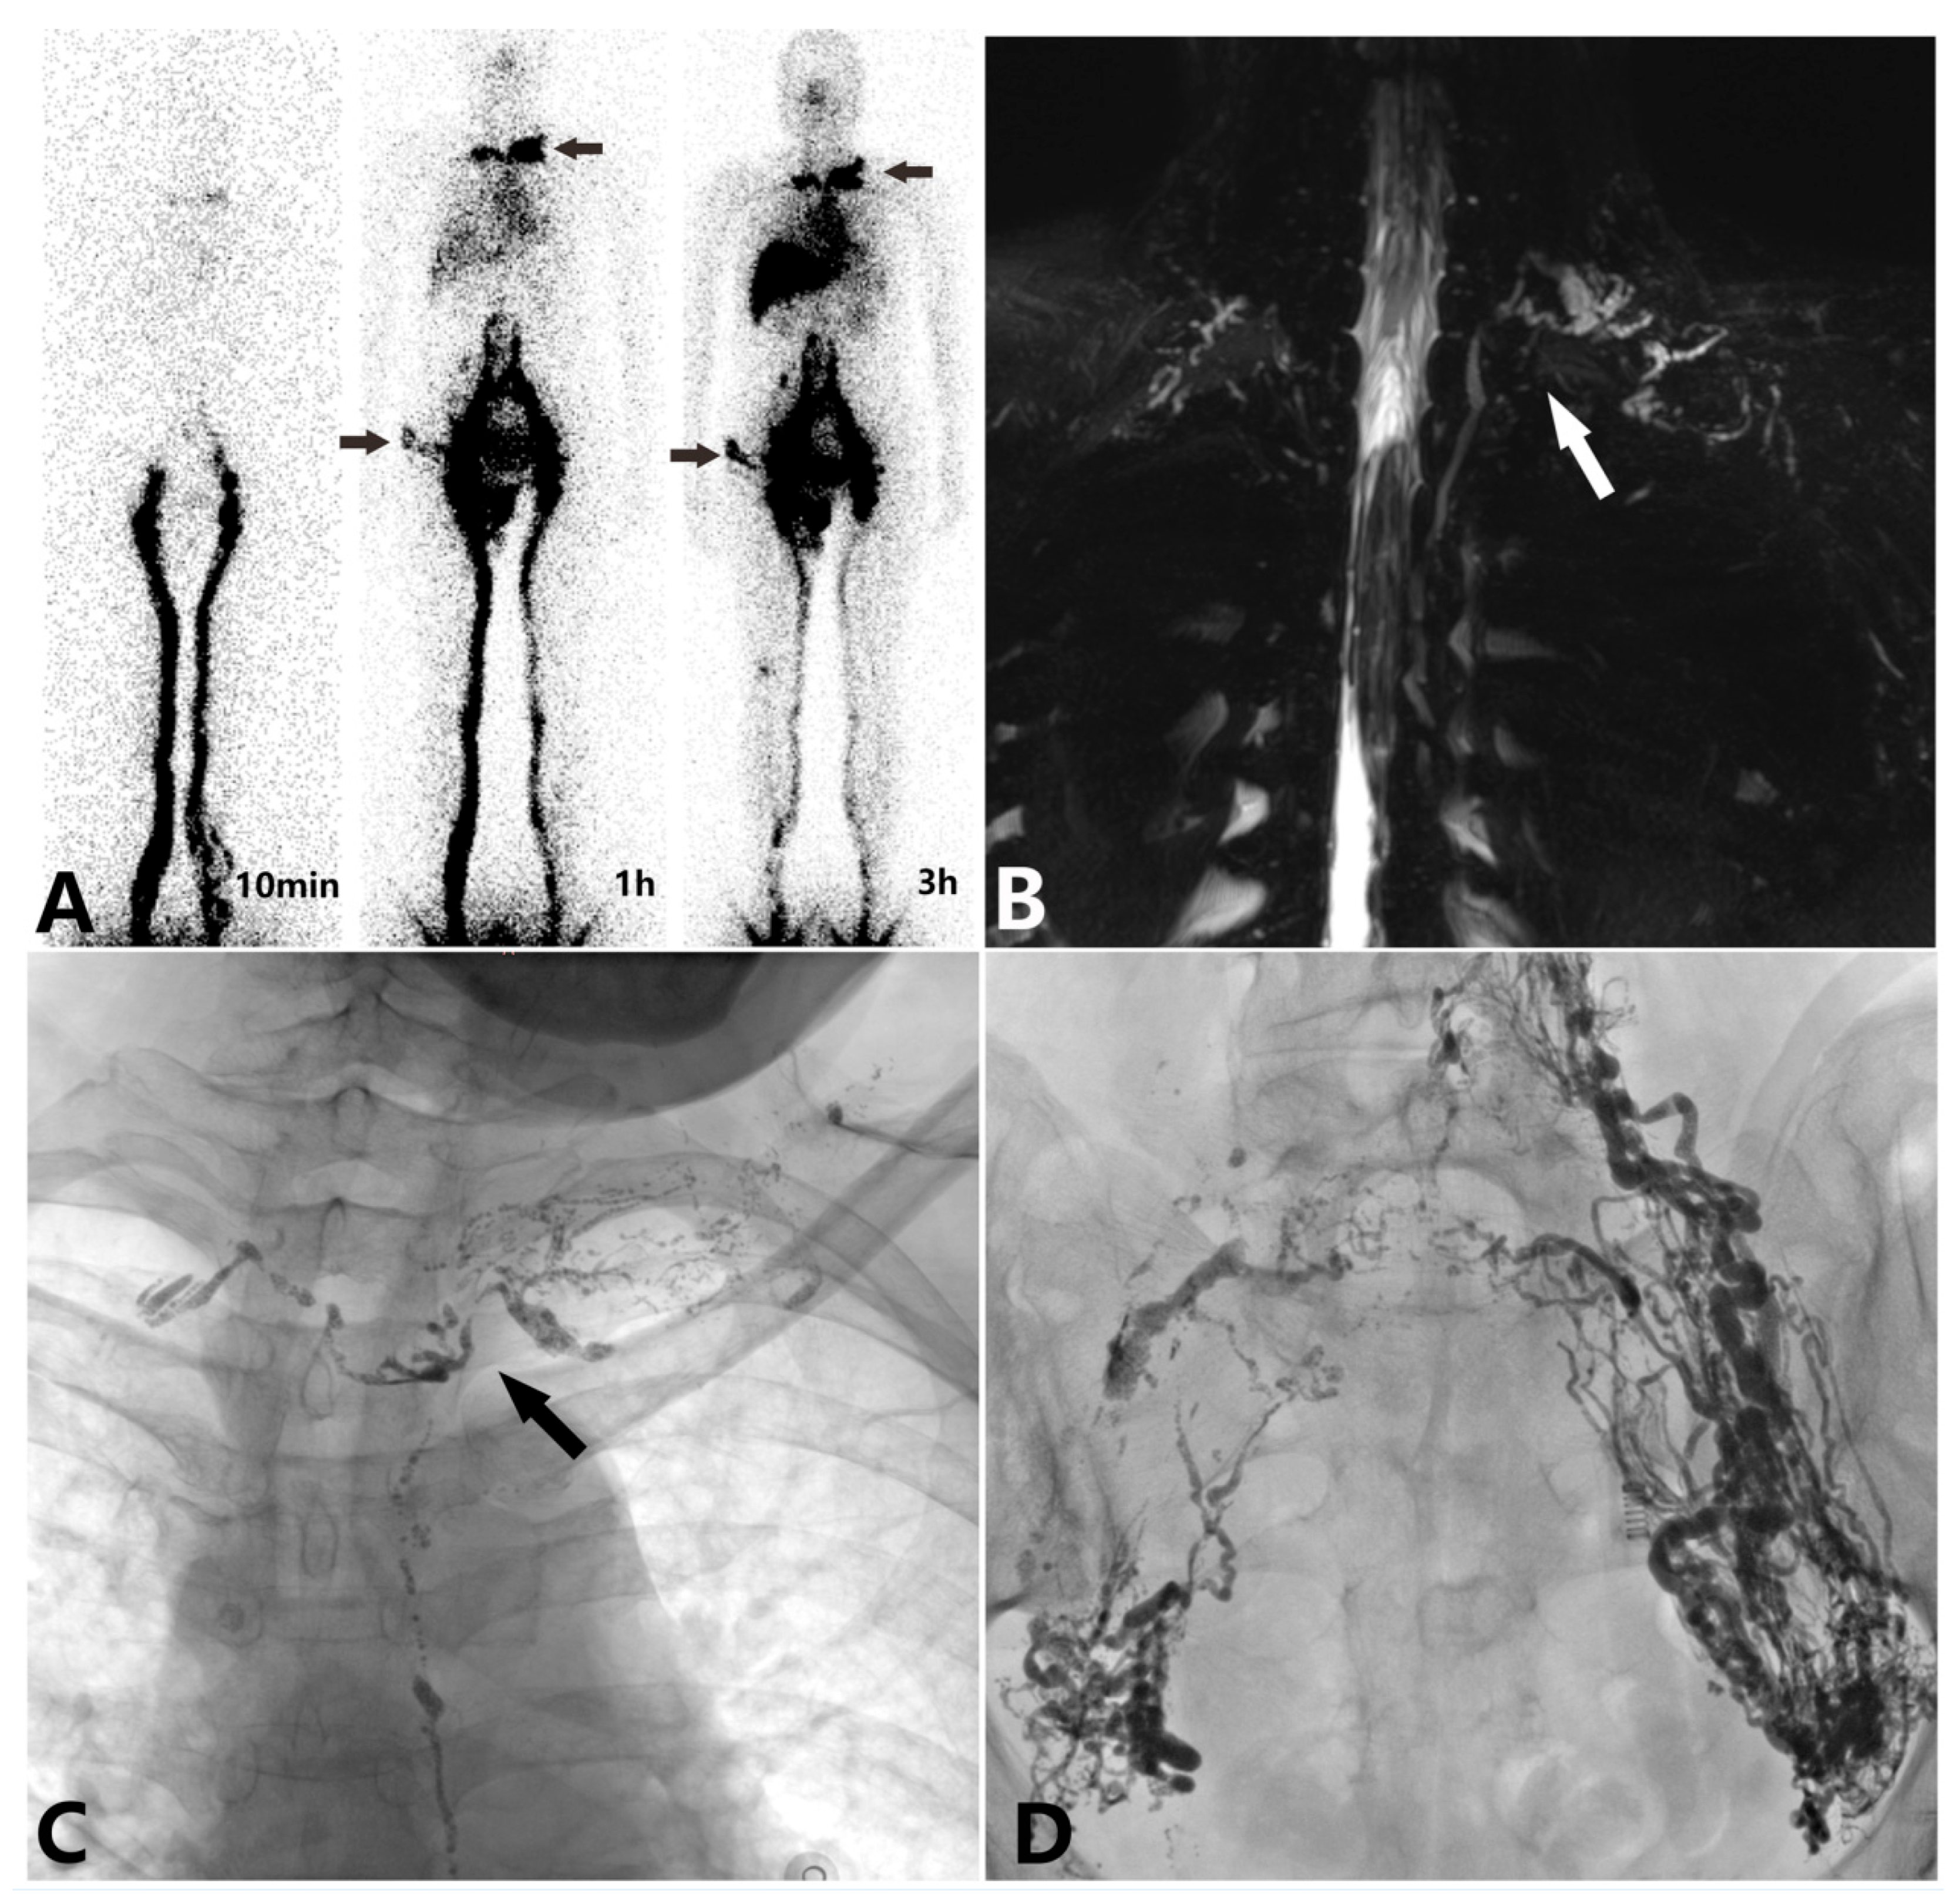

| 99Tcm-DX lymphoscintigraphy | 13 |

| Non-enhanced magnetic resonance lymphangiography | 17 |

| Intranodal lymphangiography | 18 |

| 99Tcm-DX lymphoscintigraphy | |

| Type I | 8 |

| Type II | 5 |

| Type III | 10 |

| Non-enhanced magnetic resonance lymphangiography | |

| Type I | 5 |

| Type II | 8 |

| Type III | 1 |

| Type IV | 3 |

| Intranodal lymphangiography | |

| Reasons for imaging failure | Peripheral entry of lipiodol into the bloodstream (3) Cystic dilatation of the lymphatic vessels (2) |

| TD dilatation | 16 |

| Branch reflux | 18 |

| Difficulty in lipiodol penetration into bloodstream | 18 |